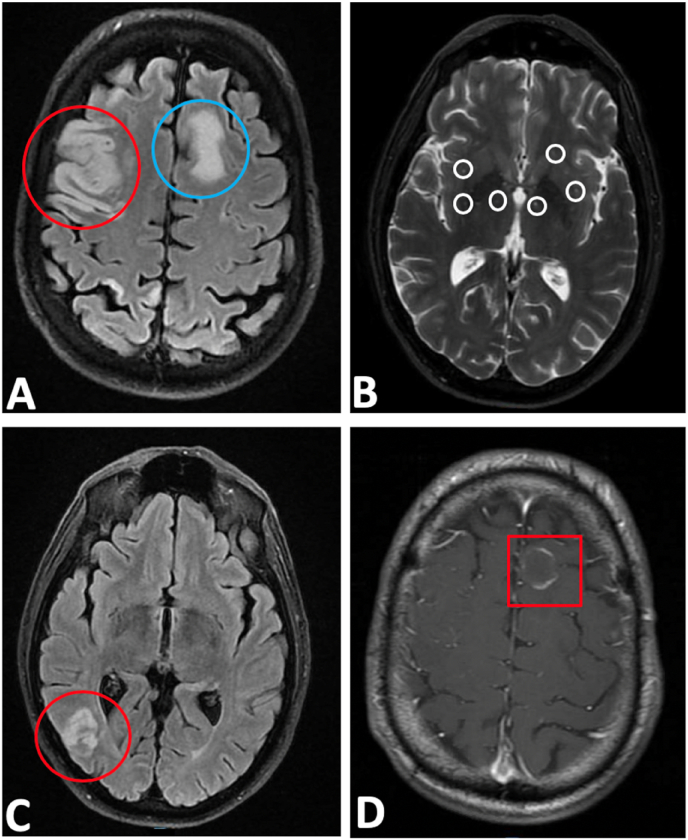

Magnetic resonance imaging (MRI) brain showed a moderate size acute infarction in the right frontoparietal lobe with small amount of internal petechial hemorrhage, numerous scattered infarctions of the right cerebral hemisphere, cerebellar hemisphere, and left frontoparietal deep white matter suggestive of embolic etiology, and a rim-enhancing lesion in the left frontal lobe with surrounding edema suggestive of metastatic disease (Fig. 2A–D). Hematology/oncology and pulmonology consultation resulted in CT chest and abdomen, showing large 8.9cm necrotic right infrahillar and lower lung mass, pulmonary embolism in distal right main pulmonary artery with extension into the right upper and lower lobe segmental artery branches, and scattered hypodensities measuring 6 mm throughout the right hepatic lobe likely representing metastasis in the setting of malignancy (Fig. 3A–B). Transthoracic echocardiogram revealed normal left ventricular ejection fraction of 55% with a 3.7 × 1.4 cm mass in the left atrium with a patent foramen ovale.

Fig. 2.

A-D: MRI brain showed: A. A moderate size acute infarction in the right frontoparietal lobe (red circle) and left frontoparietal deep white matter suggestive of embolic etiology (blue circle).

B. Small amount of internal petechial hemorrhage (white circles).

C. Numerous scattered infarctions of the right cerebral (red circle) and cerebellar hemisphere.

D. Rim-enhancing lesion (red square) in the left frontal lobe with surrounding edema suggestive of metastatic disease. (For interpretation of the references to colour in this figure legend, the reader is referred to the Web version of this article.)